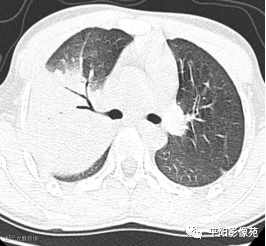

5天后复查X线片及CT:较前加重

影像特征:X线片右肺中上野片状高密度影,下缘以叶间裂为界,上缘及外侧缘模糊;CT位于右肺上叶后段,呈片状实变影,内见支气管影,边缘模糊。

影像诊断:右肺上叶大叶性肺炎。